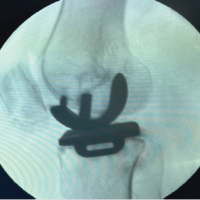

We performed re-arthroscopy and found recurrent LM tear and cartilage defect in the MFC, which corresponded to an ICRS grade 4 lesion. Therefore, we performed a partial meniscectomy of the LM and OAT of the MFC. The transplanted osteochondral plug in the LFC remained, and the ICRS cartilage repair assessment score was 10 (survival: 3, integration: 4, and macroscopic appearance: 3) (Fig. 3). In addition, the non-weight-bearing area of the lateral side of trochlear groove, which was the donor site of the primary OAT, was replaced with fibrocartilage-like tissue, and no apparent impingement was observed.